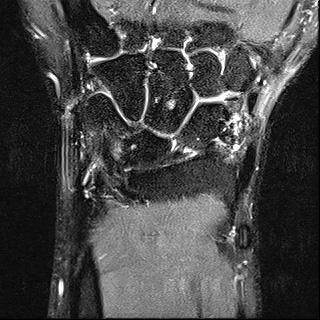

mri는 23년 부분파열 당시

• 2번 째 사진

• 제공해 주신 영상들을 확인했습니다. MRI는 2023년 부분파열 당시 촬영본이고, 단순 방사선 및 CT는 2025년 12월 골절 당시 영상으로 이해하고 검토하겠습니다.

2023년 MRI 영상을 보면, 삼각섬유연골복합체(Triangular Fibrocartilage Complex, TFCC)에 전반적인 신호 변화와 함께 척골 부착부 근처의 손상 소견이 확인됩니다. 당시 봉합술을 시행한 것은 임상적으로 타당한 판단이었습니다. 이후 경과가 양호하다가, 2025년 12월 요골·척골 원위부 골절이 발생한 점이 현재 상황의 핵심입니다.